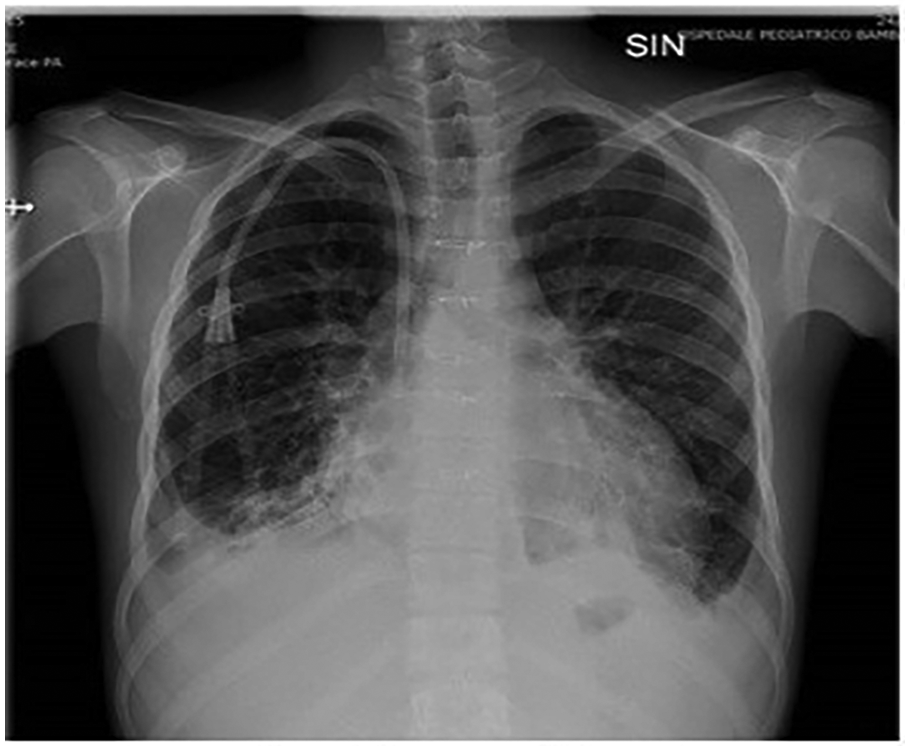

The patient was a 17-year-old boy who was previously diagnosed with a severe congenital heart disease. At 10 years of age, the patient was listed for heart transplantation and at 12 years underwent heart transplantation. At 16 years of age, the patient was diagnosed with stage 3B Hodgkin's lymphoma post-transplant lymphoproliferative disorder (HL-PTLD) associated with an Epstein–Barr virus (EBV) infection. It is an uncommon PTLD with an unclear prognosis; however, treatment with HL-specific chemotherapy is associated with improved overall survival and event-free survival. The patient received combination chemotherapy with brentuximab vedotin (an anti-CD30 monoclonal antibody) and doxorubicin, vinblastine, and dacarbazinein (BV–AVD). The doses of BV, doxorubicin, vinblastine, and dacarbazinein were 1.2 mg/kg, 25 mg/m2, 6 mg/m2, and 375 mg/m2 (once per day on days 1 and 15), respectively. During the treatment, the mycophenolate mofetile; course was interrupted. Positron Emission Tomography after 2 cycles of BV-AVD revealed a complete metabolic response; the patient received a total of 4 cycles that were well tolerated. No cardiac toxicity was observed during the treatment. At the end of the treatment, disease assessment confirmed a complete metabolic response, and EBV was not detected in the blood. However, 1 month after the last chemotherapy cycle, i.e., at 17 years of age, the patient was admitted to the intensive care unit with symptoms and hemodynamic signs of a cardiogenic shock. Three days prior to this, he had experienced a mild increase in the body temperature (37.5°C) along with decreased energy and poor appetite. Laboratory testing revealed a normal blood cell count with no increase in eosinophils and abnormal cells; furthermore, the C-reactive protein level was normal as well. Troponin I level (3,408.3 pg/ml; high-sensitivity troponin assay) and brain natriuretic peptide level (3,890.1 pg/ml) were clearly elevated, with the creatinine level, EBV CRP copy number, and everolimus level being 1.88 mg/dl, 23,793 copies/ml, and 5 μg/L, respectively. A 12-lead electrocardiogram revealed sinus tachycardia with widespread ST depression. A chest radiograph (Figure 1) revealed bilateral pleural effusion, while a 2D-echocardiogram revealed severe left ventricular dysfunction (ejection fraction: 20%). An altered diastolic function and moderate mitral regurgitation were noted, and a thickening of the myocardium that can be evocative of eosinophilic infiltration (Figure 2). The right ventricular function was also impaired (right ventricular fractional area change, 20%; tricuspid annular plane systolic excursion, 12 mm) with severe tricuspid regurgitation and elevated right ventricular pressure. Thin layers of pericardial effusion and moderate bilateral pleural effusion were also noted. Therapy for acute heart failure was initiated intravenously using inotropic drugs (milrinone, adrenaline, vasopressin, and levosimendan); their doses were determined using an internal protocol. The patient underwent cardiac catheterization, coronarography, and endomyocardial biopsy (EMB) of the right ventricle. Coronarography was negative for obstructive lesions, and no intravascular ultrasound was performed at this time; however, the most recent study revealed a Stanford II coronary artery vasculopathy. Owing to the rapidly worsening hemodynamic stability, arteriovenous extracorporeal membrane oxygenation (ECMO) was initiated. During ECMO, the clinical conditions were critical but more stable.

Figure 1

Chest radiograph shows bilateral pleural effusion.